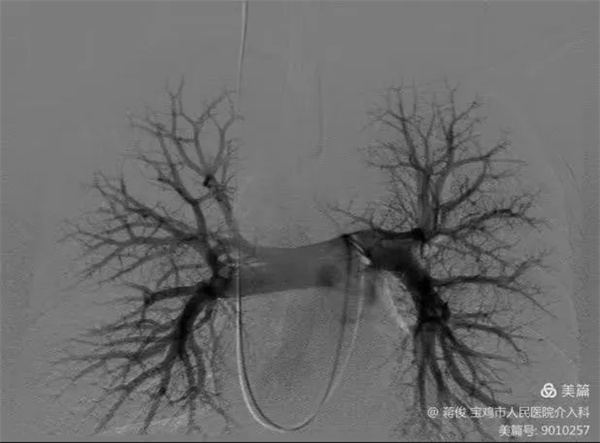

規律抗凝半年后,復查肺動脈DSA造影提示肺動脈血栓完全消除,同期取出下腔靜脈濾網